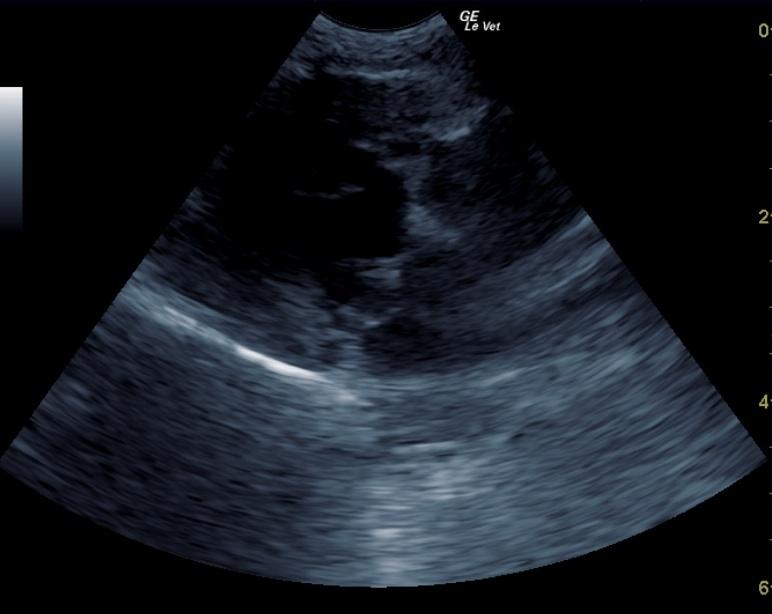

A 10 year old female spayed Maltese was presented for excessive urination. The only significant abnormality on physical examination was a grade II/VI systolic heart murmur. On urinalysis, an inappropriate SG and 2+ proteinuria was present. CBC was within normal limits, but blood chemistry showed elevated ALT activity and azotemia. T4 was 1.2.